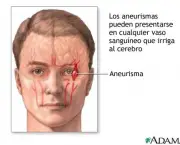

O Aneurisma Cerebral pode ser definido basicamente como uma dilatação anormal de uma das artérias do cérebro. Essa dilatação pode levar a ruptura dessa artéria, o que gera sangramentos que seguem para um espaço do cérebro chamado de “espaço subaracnóide”.

Esse aneurisma pode aumentar e se romper, essas formações podem se romper em qualquer momento da vida, mas é mais comum na quarta ou quinta década da vida. As mulheres possuem mais chances de desenvolver aneurismas do que os homens e em mais de 20% dos pacientes é possível observar a existência de mais de um Aneurisma Cerebral.